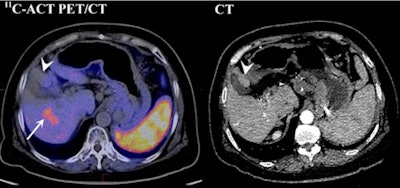

| Contrast-enhanced CT shows nodule impinging on gallbladder, suggesting an HCC (arrowhead) with no abnormal metabolism on C-11 acetate PET/CT. However, a C-11 acetate-avid lesion (arrow) was found. Results of pathological analysis for excised liver confirmed 3.6-cm HCC in right lobe and dysplastic nodule of 2 cm in the left lobe adjacent to the gallbladder. Image courtesy of the Journal of Nuclear Medicine. |

The lower results with contrast-enhanced CT were related to cirrhosis or previous treatment, which can hamper the differentiation of cirrhotic nodules from HCC lesions and the estimation of tumor size, Cheung and colleagues noted.